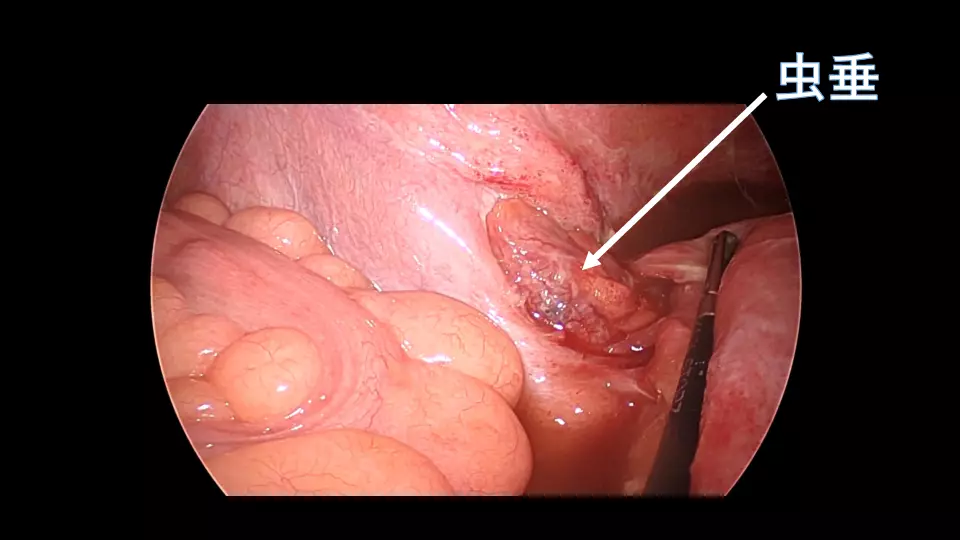

「反跳痛があります」と記載された紹介患者や、研修医からコンサルトにおいて、意外と腹膜炎ではないパターンが散見されます。 若手外科医だからこそ語れる腹膜炎のはなしを聞いてください。 #腹膜炎,#反跳痛の診かた,#コンサルト,

外科医目線の腹膜炎 ~これが腹膜刺激兆候です~